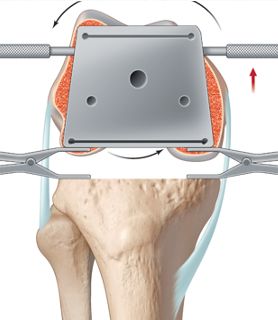

1.3 Extension gap first technique

This technique (also known as combined or mixed technique) combines landmarks and soft tissues for the proper rotational alignment and sizing of the femur component. It was introduced more than 15 years ago since many surgeons recognized the several limitations of the classical two techniques [34,35]. The distal femur and proximal tibia cut are performed perpendicular to the mechanical axis and the neutral frontal mechanical alignment is controlled. The extension gap is balanced now by soft tissue releases until it is rectangular and stable (extension gap first technique). During the next step the femur rotational alignment and sizing is determined either by the classical bony landmarks or the balanced gap technique. By either technique both the landmarks and ligaments are used to control each other. Only if both are matching the final anterior-posterior cuts for the femur are performed (Fig 5). This was a big step forward for controlling the proper rotational positioning and sizing of the femur component before cutting the femur.

In our experience the best option to correct axial plane deformities at the distal femur is by using the extension gap first technique [34]. After performing the extension gap bony cuts for neutral alignment, a balanced extension gap can be achieved by proper soft tissue releases. After the proper frontal alignment is controlled and the extension gap is balanced the knee is flexed to 90°. The femur anatomy (anterior or posterior axial plane deformity) can be easily identified, and several anatomical combinations exist (Fig 11 and 13).

The AP and TEA lines are drawn on the distal femur and the natural flexion gap can be checked by using tensioner or spreaders. This allows to decide how much ER will be needed to bring the component parallel to the TEA. For axial plane deformities we place the femur component always parallel to the TEA to correct any anterior or posterior axial femur pathology. With this simple technique any axial plane deformity of the distal femur can be corrected (Fig 15).

After placing the 4in1 cutting block the future flexion gap can be checked again by using spacer blocks, tensioner or laminar spreaders and will be already symmetric. In cases with extensive releases necessary for the extension gap the soft tissue frame cannot be used anymore to check the proper rotational alignment of the flexion gap. After insertion of the trial components and temporary closure of the arthrotomy a dynamic testing of the flexion gap has to be performed with the number of 4 test. In the rare situation where the fix bearing PS is dislocating and the flexion gap is not stable anymore, we switch to a super stabilized PS or semiconstraint implant with CCK insert.